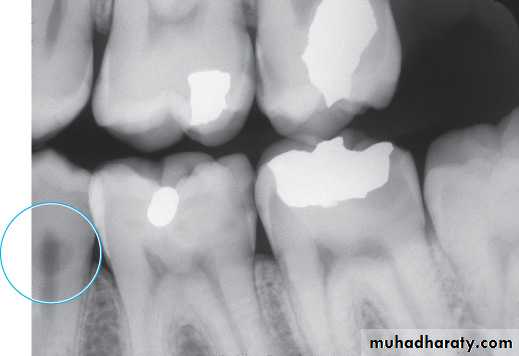

Bitewing radiograph. This radiograph shows (1) large occlusal caries, (2) radiolucent lines or mach band effect (an optical illusion caused by overlapped enamel), (3) interproximal caries, and

(4) cervical burnout